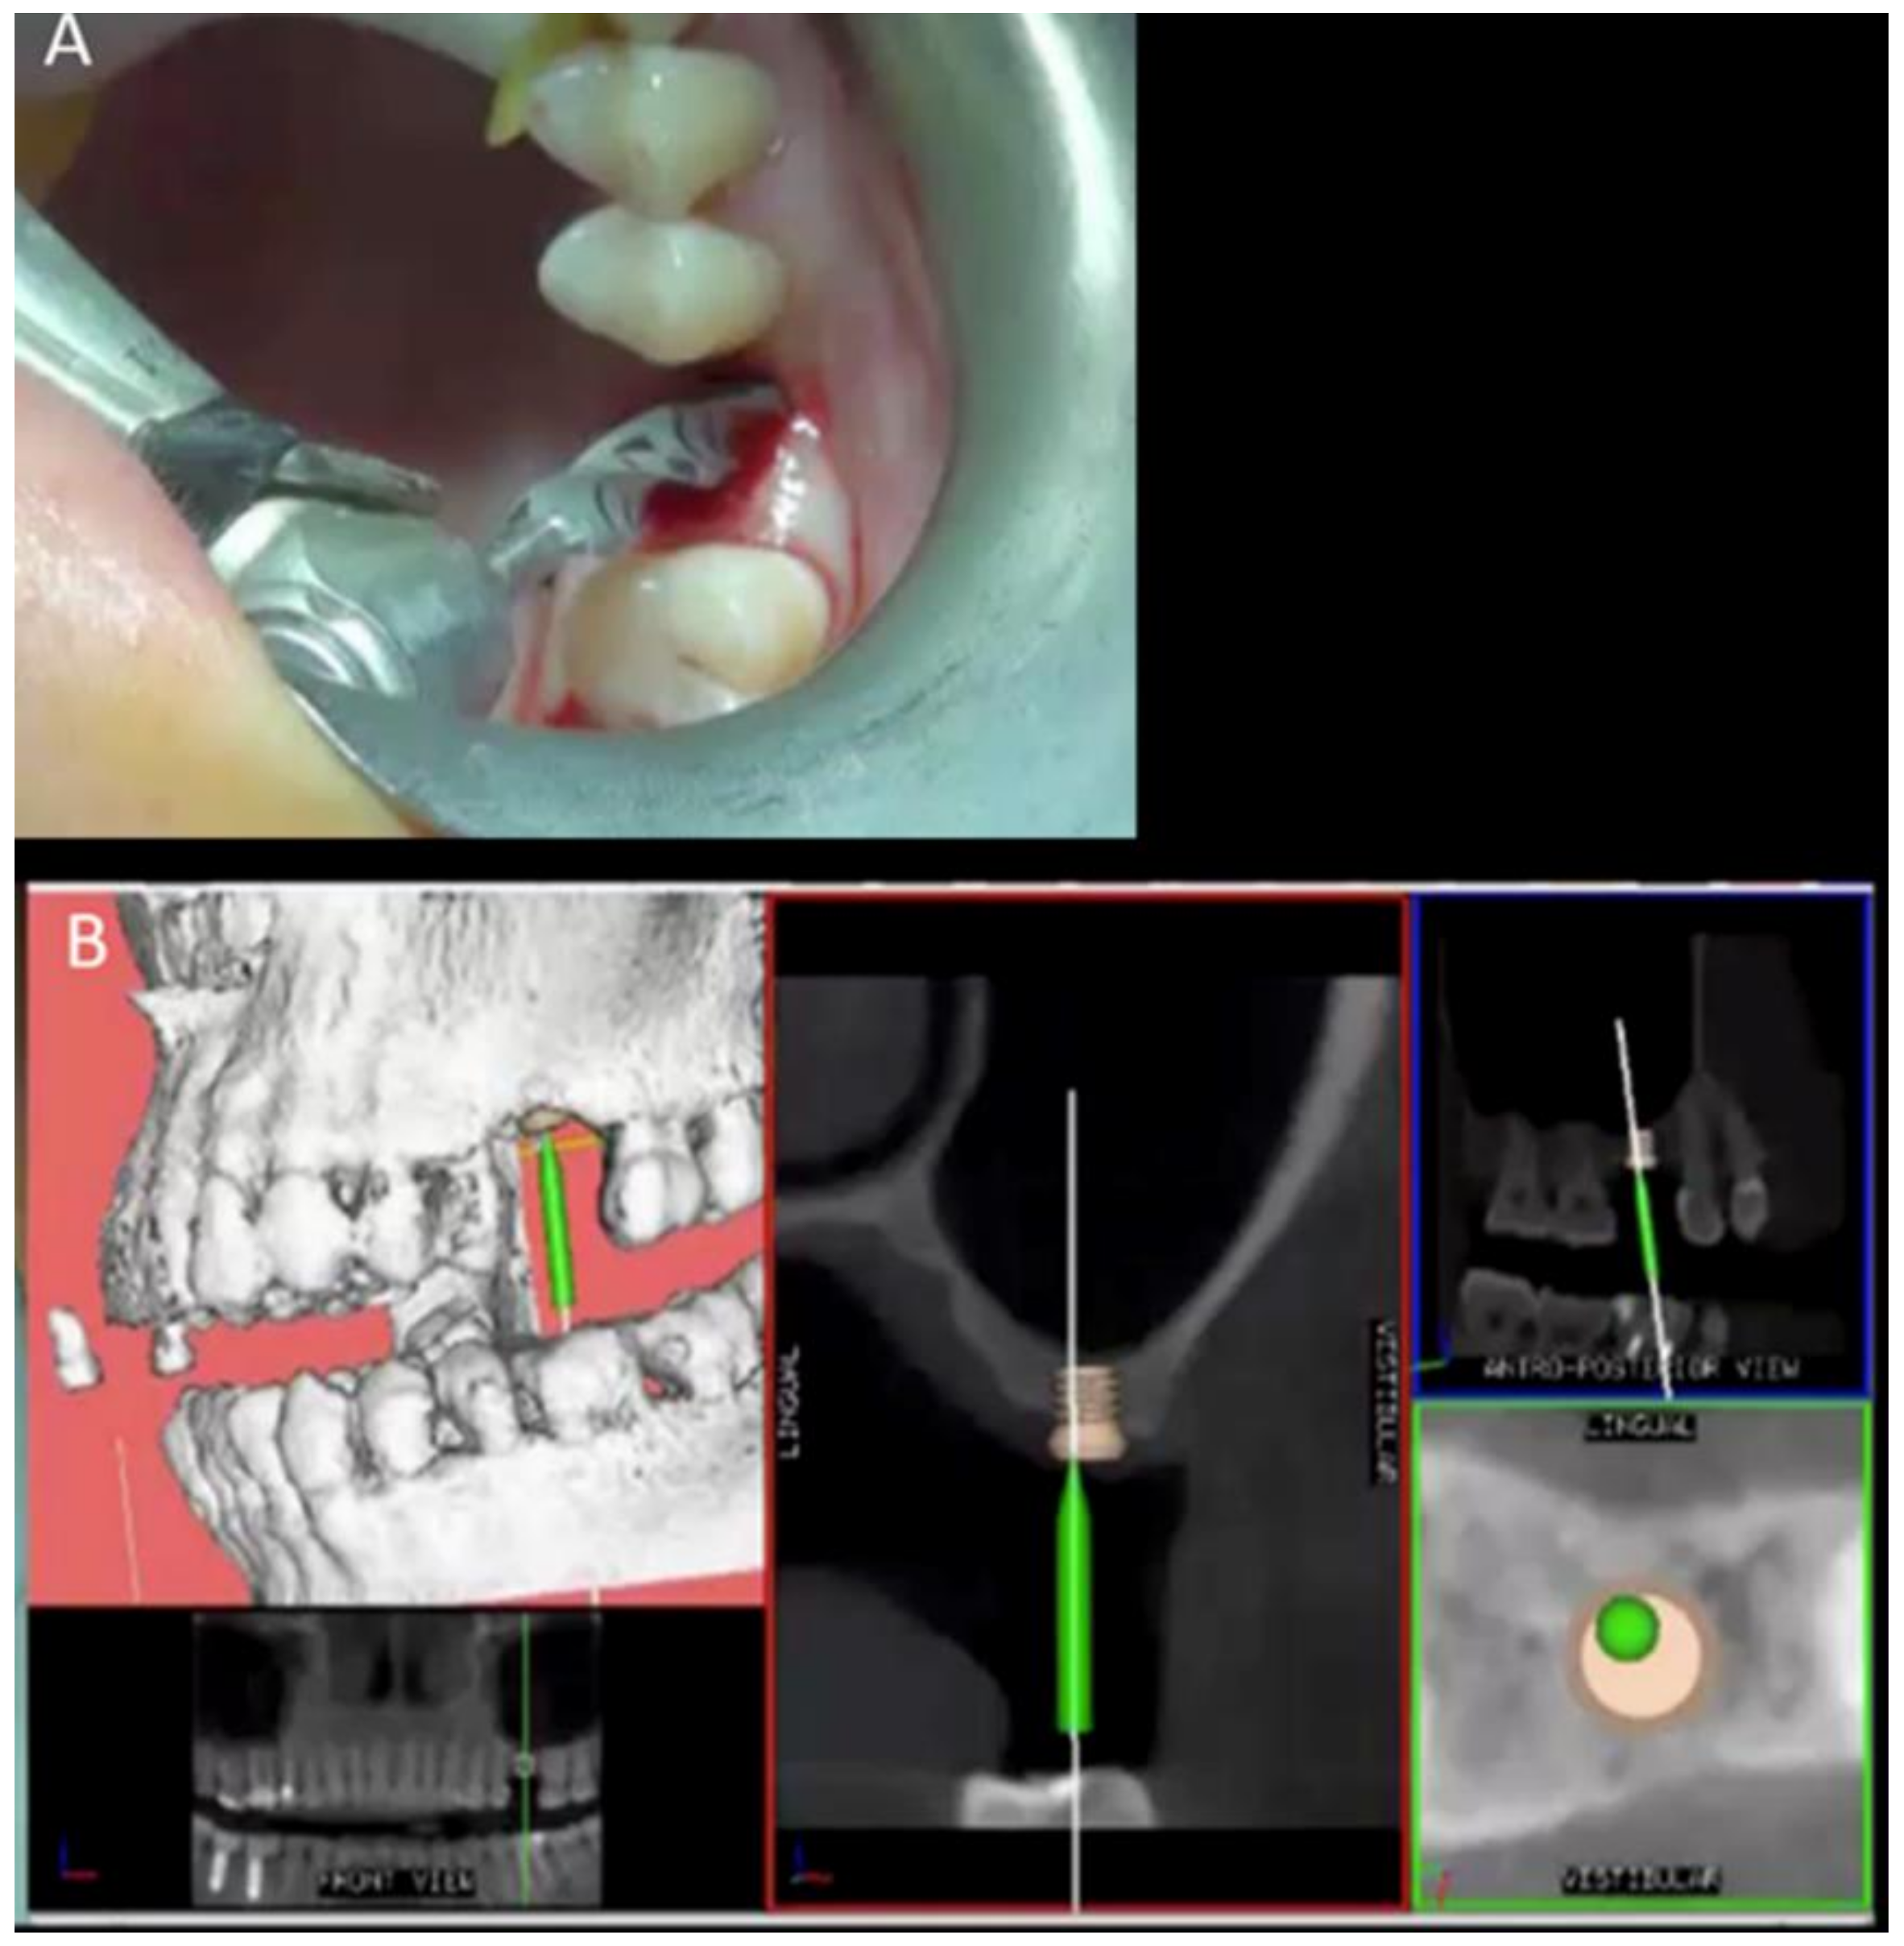

2.2. Surgical and Prosthetic Procedure